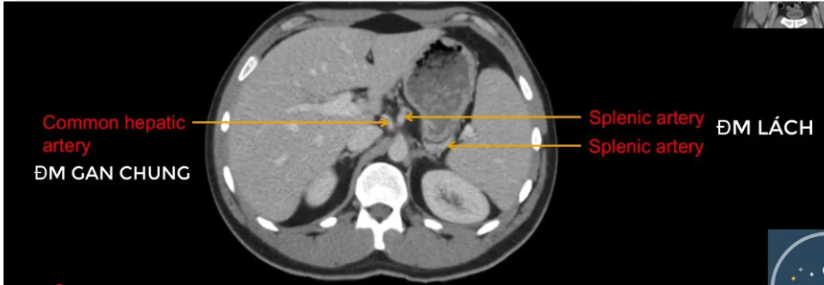

TM gan ở đâu? TM chủ dưới ? ĐM chủ?